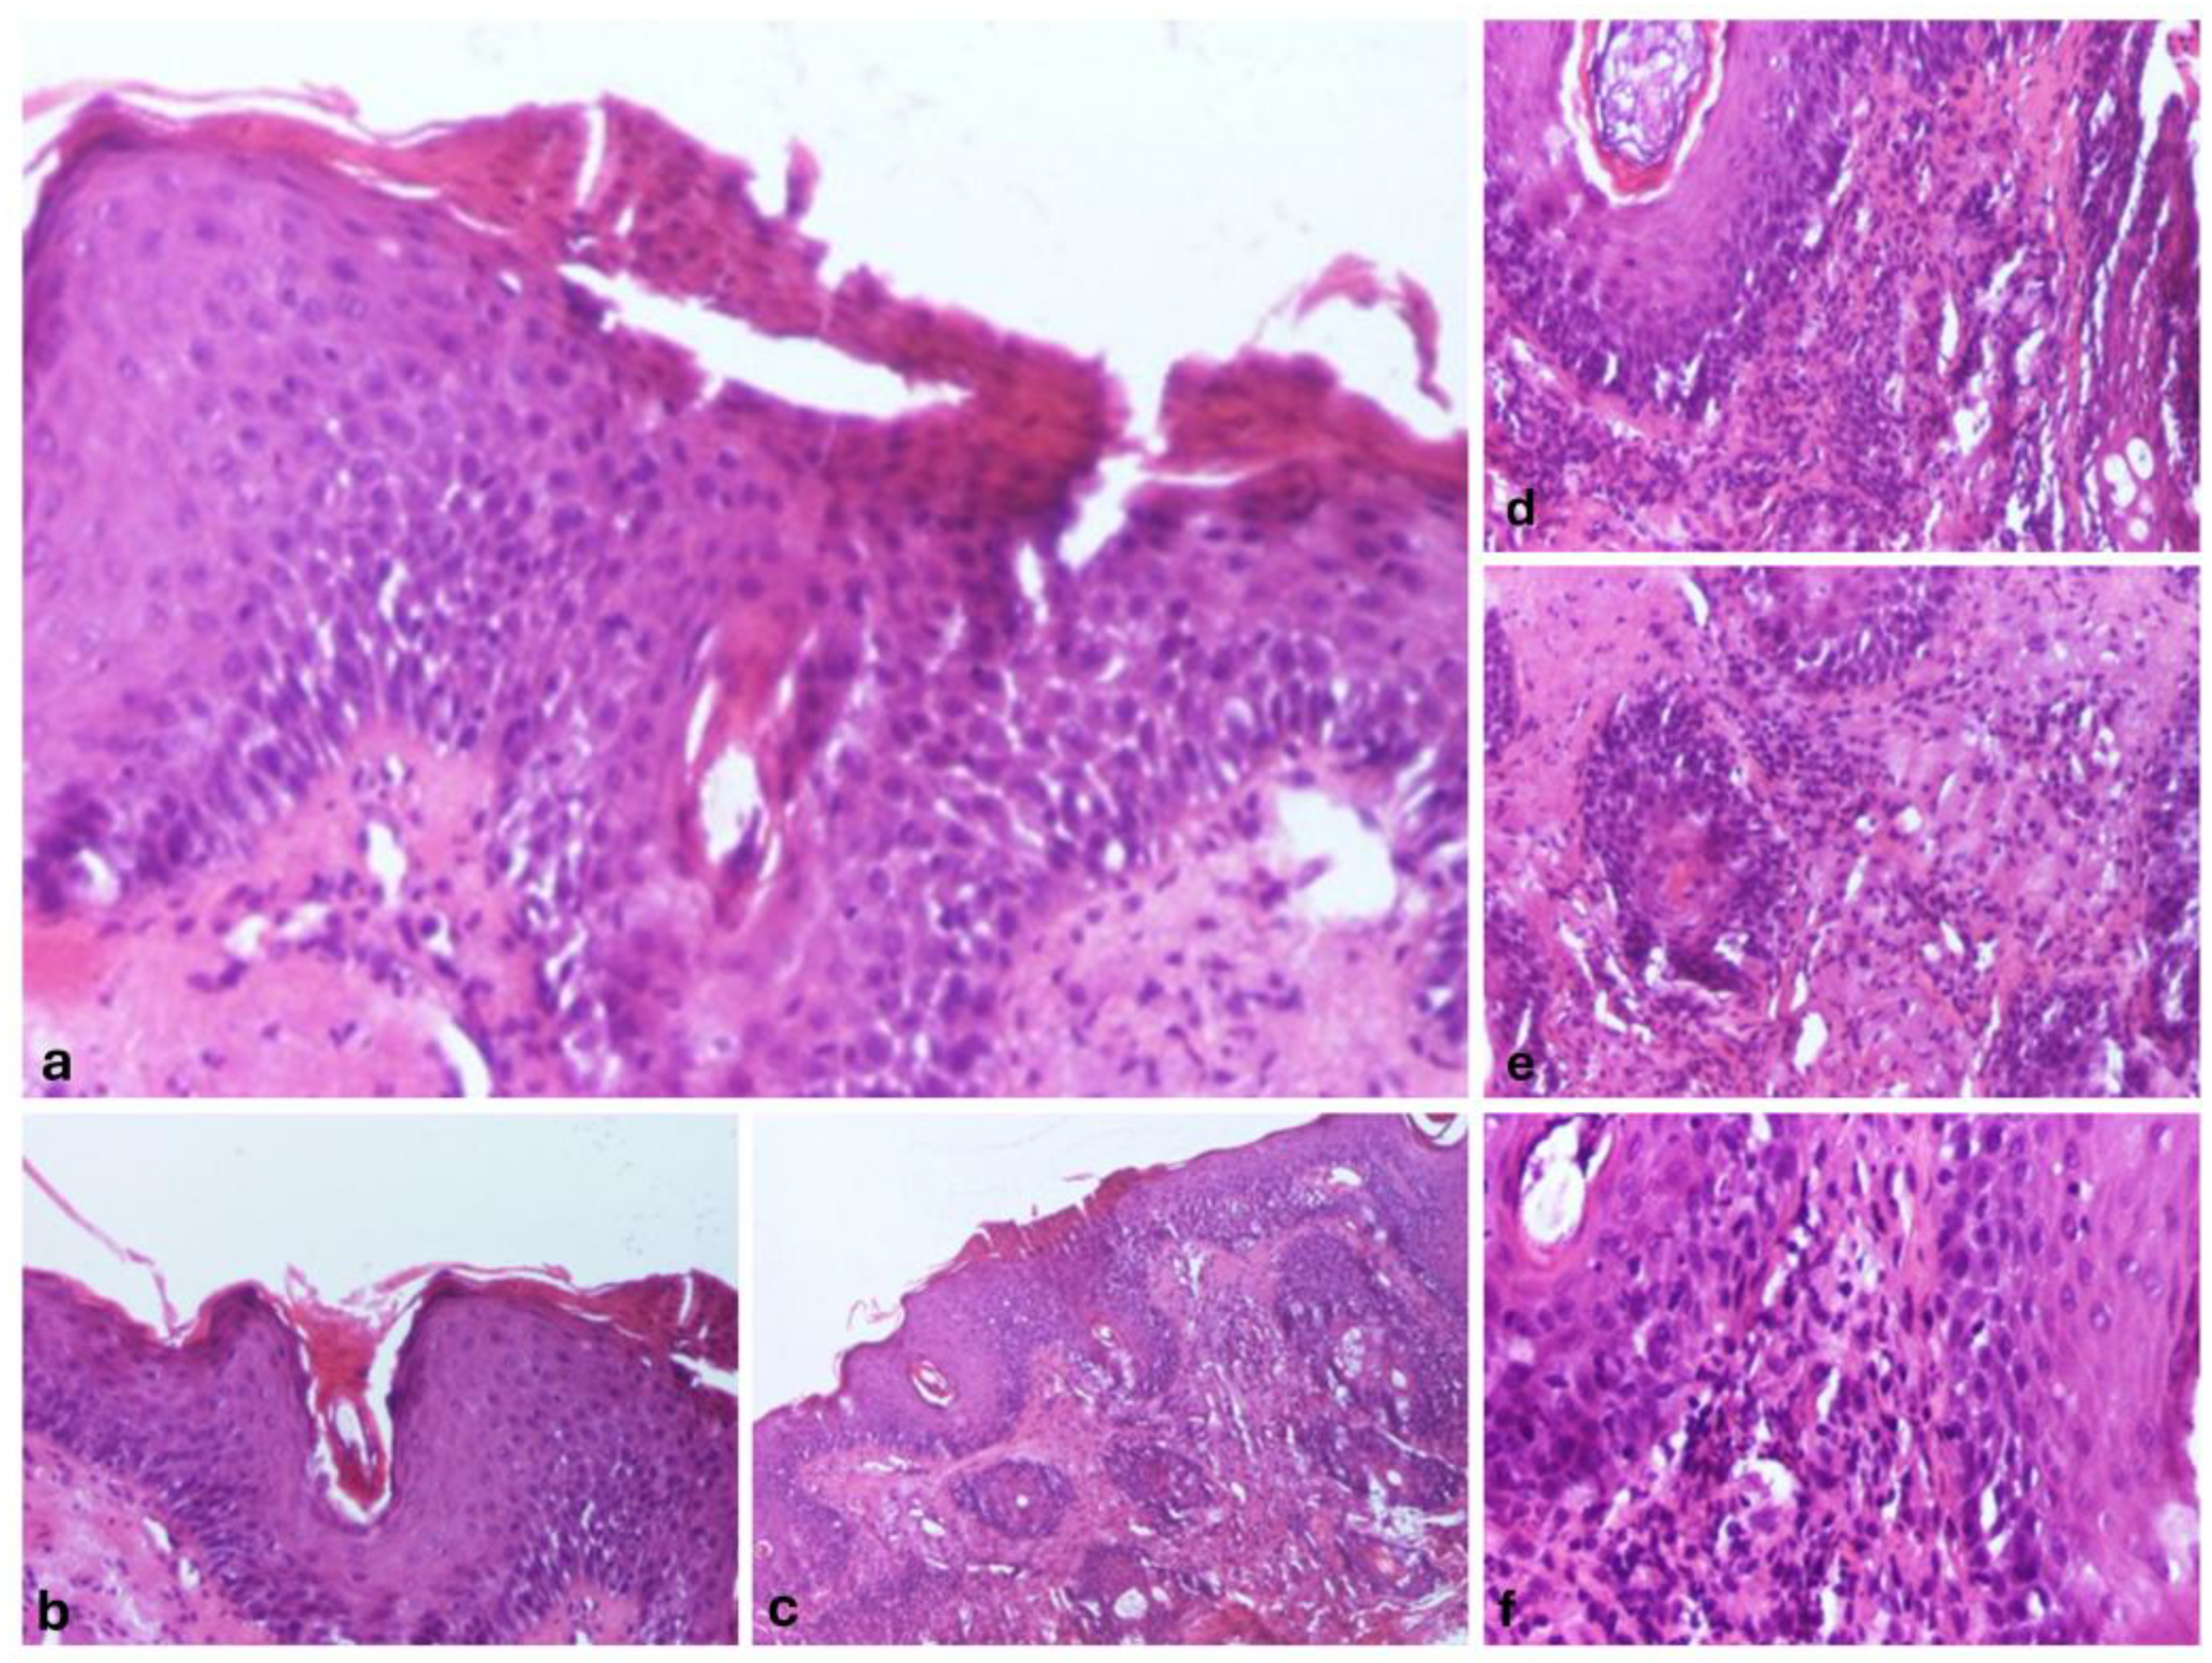

We also performed a skin biopsy (Figure 2) that revealed an ortokeratotic epidermis with focal areas of parakeratosis at the follicular openings (Figure 2a,b), irregular acanthosis, and focal spongiosis (Figure 2c). Numerous pilosebaceous follicles were observed, surrounded by a dense inflammatory infiltrate composed of lymphocytes and neutrophils, with their infiltration into the surrounding tissue (Figure 2d–f).

Figure 2. Morphopathological features revealed: Epidermis with orto- and parakeratosis, Hematoxylin and Eosin (HE), 100x magnification (a), follicular hyperkeratosis, with keratinous material filling the infundibulum of the hair follicles, HE, 100x magnification (b), epidermis with irregular acanthosis, and focal spongiosis, HE, 40x magnification (c), Superficial perivascular and perifollicular infiltrate, primarily composed of lymphocytes, with occasional neutrophils, HE, 100x magnification (d), follicular epithelium damage with the dermal region surrounding the follicle infiltrated by a mixture of lymphocytes and neutrophils, HE, 100x magnification (e), perivascular and perifollicular infiltrate, primarily composed of lymphocytes, with occasional neutrophils, HE, 100x magnification (f).